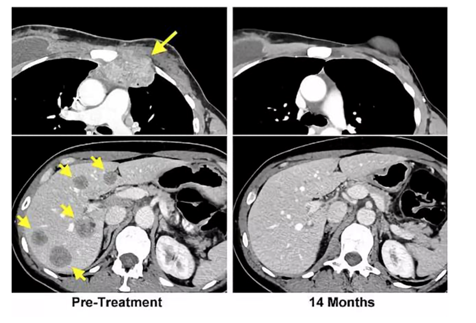

△該患者體內(nèi)各處的腫瘤體積縮小

在22個月后,該患者體內(nèi)各處的腫瘤體積就大幅縮小,在結束治療的14個月后,復查也顯示,該名患者原發(fā)部位的腫瘤消失了。